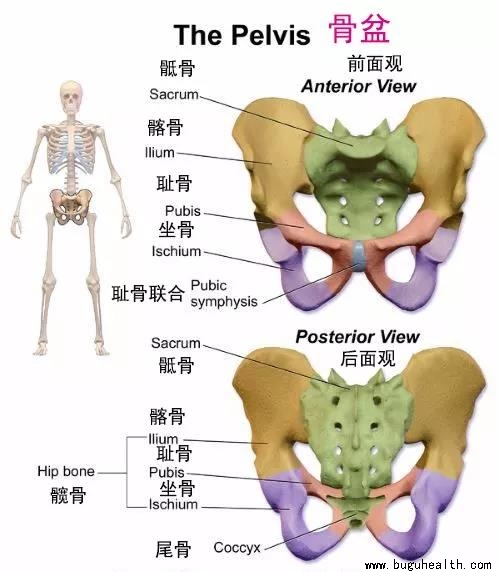

- 骨盆是人体的重要结构之一,承受着上半身的重量,又控制着下半身的动作。有几十条肌肉组织相连。对调节身体姿势起着重要作用。而与骨盆密切相关的盆底肌与身体的健康息息相关。很多人都不太知道盆底肌用力是什么感觉。关于盆底肌,经常听到的引导方式有:① 想像一个手帕,从中心点被往上拉起来的感觉 ② 想像就像一个帐.....

- “假胯宽”听起来好像是在说胯过宽的问题,其实并非如此。“胯”在我们身体骨盆外侧最高点的位置――髂骨两侧的边缘。所以,胯的宽度,就是髂骨两侧边缘的距离。而所谓“假胯”,就是说突出的位置并不是真的胯,而是因为那里过宽,让我们误以为是胯,所以被称为“假胯宽”。 “假”胯,位于真“胯”的下方,位于大腿根部.....

- 与骨盆有关的常见烦恼就是骨盆“歪斜”。而骨盆之所以歪斜,是因为肌肉不平衡,而并非骨骼本身变形。 最近经常有产后妈妈咨询,说自己骨盆歪了,我们有什么仪器帮助她,听说某某机构一次正骨就好了。听的我一头雾水,作为康复治疗师,从人体解剖结构上来讲我认为这些都是营销噱头,因为除去疾病状态骨骼本身并不会歪.....

- 布骨医学科普:为什么骨盆会产生歪斜? 布骨康复医疗中心董月 ,2020-07-11

- 引起骨盆歪斜的原因: 1. 扭伤、受伤没有痊愈,带着旧伤继续行走生活; 2. 先天性的O型腿、扁平足、加上体重过重、运动过度所致; 3. 长时间跷二郎腿,驼背坐姿电脑前办公; 4. 腹肌、背肌力量弱,坐椅子时没有坐到底,但又喜欢靠着椅背; .....

- 盆底解剖结构,女性盆底是由封闭骨盆出口的多层肌肉和筋膜构成,有尿道、阴道和直肠贯穿其中。盆底肌肉群、筋膜、韧带及其神经构成了复杂的盆底支持系统,其互相作用和支持,承托并保持子宫、膀胱和直肠等脏器在盆腔的正常位置。若盆底结构和功能发生异常,可影响盆腔脏器位置及功能,甚至引起分娩障碍,而分娩处理不当,亦.....